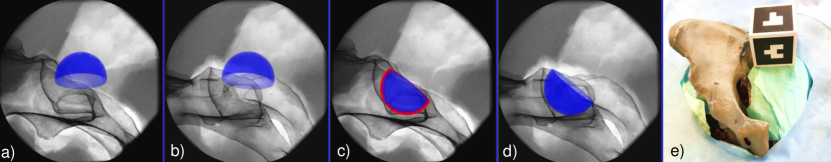

The planning of an acetabular cup based on two X-ray images is shown in Fig. 3.

Refer to caption

Figure 3: The acetabular component is forward projected from an initial 3D pose onto the respective X-ray image plane  (a-b). The surgeon moves the cup until satisfied with the alignment in both views (c-d). The X-ray images shown here are acquired from a dry pelvis phantom encased in gelatin. A cubic visual marker is placed near the phantom but outside the X-ray field of view to track the C-arm (e).